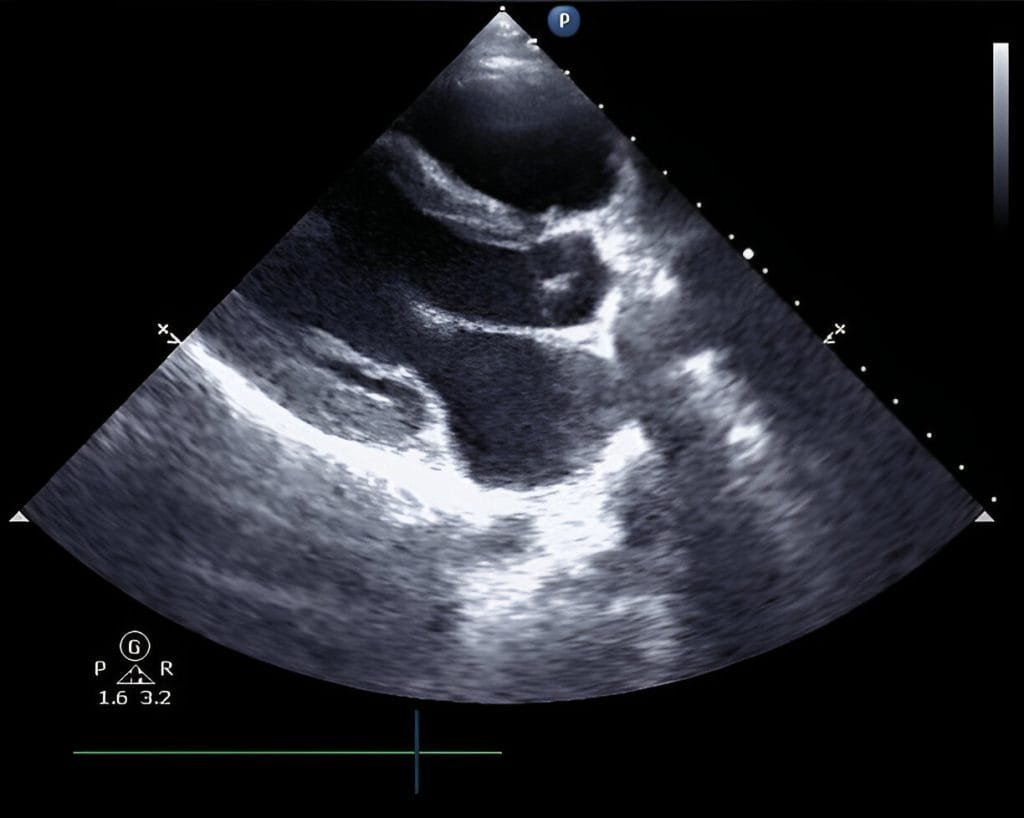

• Echocardiogram: An Echocardiogram or the echo test uses ultrasound to provide the heart’s detailed images of heart structure and function. This helps determine any abnormalities in the heart.

Echocardiogram